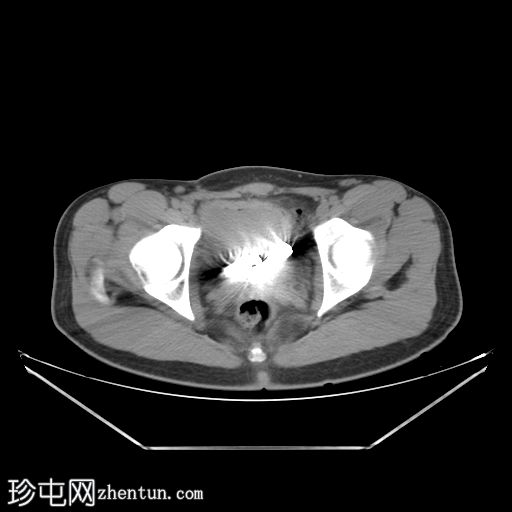

CT扫描

膀胱内可见两个圆柱形金属物体,导致金属伪影。